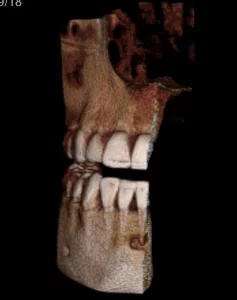

A CBCT was taken after a negative cold test indicated a necrotic tooth. When the CBCT was taken, we could clearly see that the abscess had completely perforated the labial bone at the apex of #24 and was close to doing so on #25.

As we investigated more deeply, we identified another critical piece of information that would affect our treatment plan: a second canal on #24.